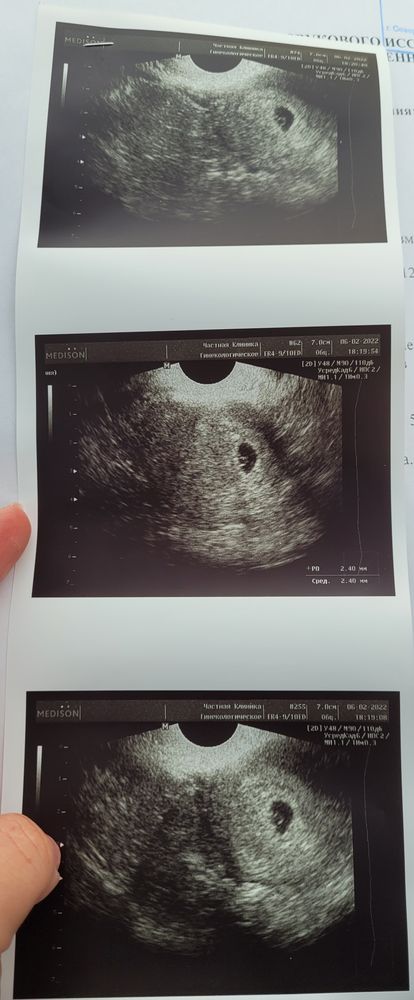

Всем привет. Ну вот и сделала узи. Не хотела делать до 5 недель. В итоге пошла сделала потому что сегодня начало мазать коричневым. Там все хорошо тьфу тьфу. Эрозя кровит слегка